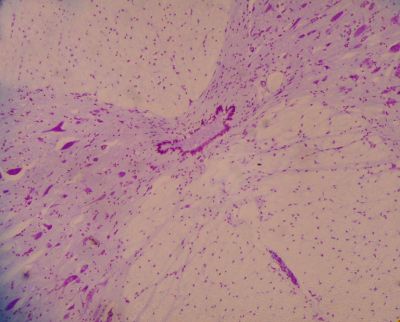

Spinal cord - histology slide

This is a histology slide from the spinal cord.

Histology slide courtesy of Florida State University.

Central Nervous System Histology - Spinal Cord